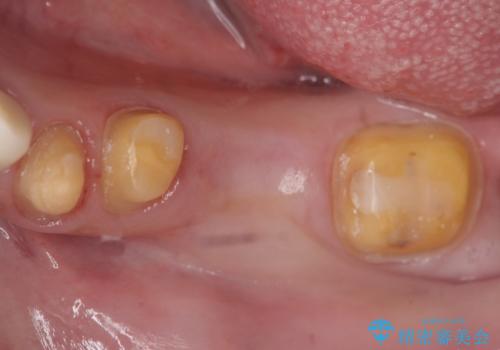

- 左下の銀歯を前の歯に合わせて白くしたいといらっしゃった方の症例です。

前歯部のシェードに合わせ、左下4及び左下567ブリッジをオールセラミッククラウンにて補綴しました。